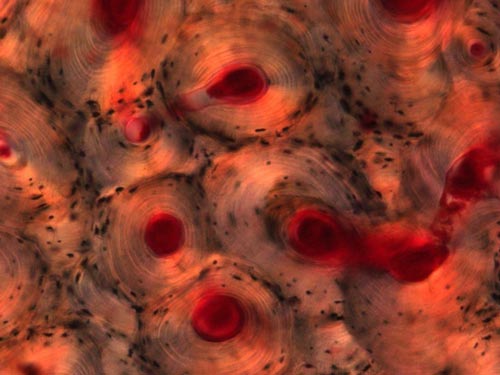

14 人體股骨的密質骨骼

如圖所示,這是人體股骨的密質骨骼圖像,其中顯示出包含血管和結締體素的微型管道網絡。密質骨使人體骨骼堅硬有力,它是由多層有機物質和無機鹽構成的。

存活的密質骨細胞在樣本制備過程中已被摧毀,留下小孔。空氣充斥在在這些小孔之中,由于視覺折射作用使用這些小孔呈現出黑色。圖片是由艾弗-梅森(Ivor Mason)拍攝并提供的。

This image of compact bone from a human femur shows a network of tiny canals that contain blood vessels and connective tissue. Compact bone provides strength and rigidity in the body, and is composed of a layered matrix of organic substances and inorganic salts. Living bone cells are destroyed during specimen preparation, leaving tiny holes. Air is often trapped inside these holes, giving the cavities a dark appearance because of optical refraction. (Image: Ivor Mason) [NewScientist]